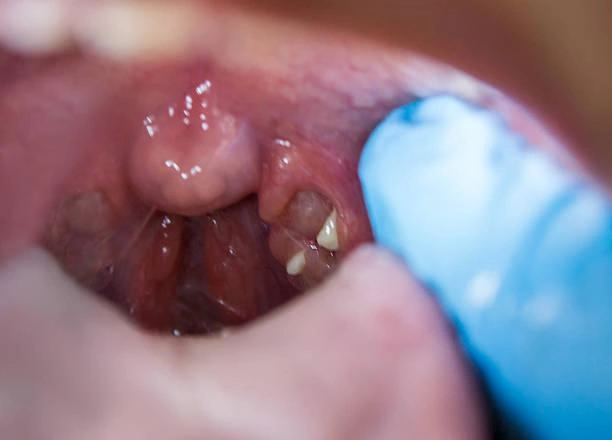

Um dos procedimentos realizados na clínica é a cirurgia de adenoide pelo plano de saúde, que tem como objetivo tratar problemas relacionados à adenoide, um tecido linfático importante para a defesa do organismo.

A cirurgia de adenoide é recomendada em casos de obstrução nasal, dificuldade respiratória, infecções frequentes, entre outros problemas que podem afetar a qualidade de vida do paciente.